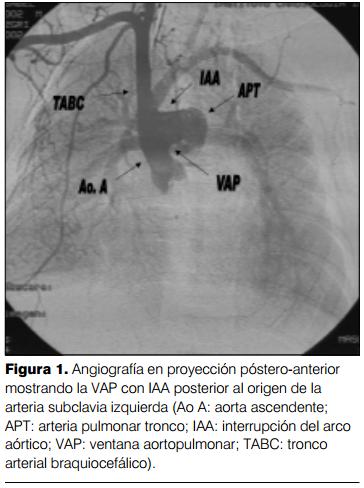

Cateterismo cardíaco (aortografía retrógrada) por vía arteria humeral derecha: a) interrupción del arco aórtico tipo A; b) ventana aortopulmonar tipo I, con importante cortocircuito de izquierda- derecha. Ductus arterioso permeable de pequeño calibre. Hipertensión arterial pulmonar a nivel sistémico con gradiente arteria pulmonar-ductus-aorta descendente de 30 mmHg. Dilatación de arteria pulmonar y cavidades izquierdas. FEVI normal (figuras 1, 2 y 3).